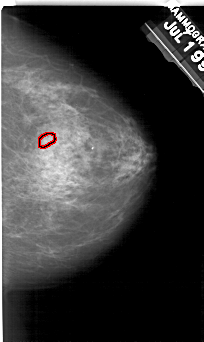

ics_version 1.0 filename A-1944-1 DATE_OF_STUDY 19 7 1994 PATIENT_AGE 72 FILM FILM_TYPE REGULAR DENSITY 3 DATE_DIGITIZED 8 7 1999 DIGITIZER HOWTEK 43.5 SEQUENCE LEFT_CC LINES 5431 PIXELS_PER_LINE 3106 BITS_PER_PIXEL 12 RESOLUTION 43.5 NON_OVERLAY LEFT_MLO LINES 5491 PIXELS_PER_LINE 3406 BITS_PER_PIXEL 12 RESOLUTION 43.5 NON_OVERLAY RIGHT_CC LINES 5116 PIXELS_PER_LINE 3046 BITS_PER_PIXEL 12 RESOLUTION 43.5 OVERLAY RIGHT_MLO LINES 5491 PIXELS_PER_LINE 3391 BITS_PER_PIXEL 12 RESOLUTION 43.5 OVERLAY |

FILE: A_1944_1.RIGHT_CC.OVERLAY TOTAL_ABNORMALITIES 1 ABNORMALITY 1 LESION_TYPE CALCIFICATION TYPE PLEOMORPHIC DISTRIBUTION CLUSTERED ASSESSMENT 4 SUBTLETY 3 PATHOLOGY BENIGN TOTAL_OUTLINES 1 BOUNDARY |